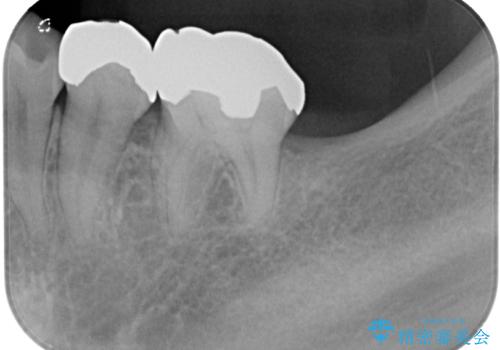

長い期間歯が欠損していた下顎奥歯に、インプラント埋入と同時に仮歯を装着すると(埋入即時荷重インプラントを行うと)、舌の付け根で仮歯を横向きに押してしまい、インプラントが脱落する危険性が高くなります。

インプラント埋入時に、装着できる状態の仮歯を用意するものの、埋入後すぐには加重させず、インプラントが無事に生着したことを確認した後に装着することで、危険を回避しつつ外科処置や痛みの少ないスムーズな治療を行うことができます。